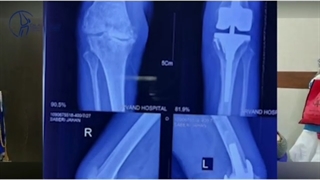

عمل جراحی تعویض مفصل ران در بیمار ۵۷ ساله⭕